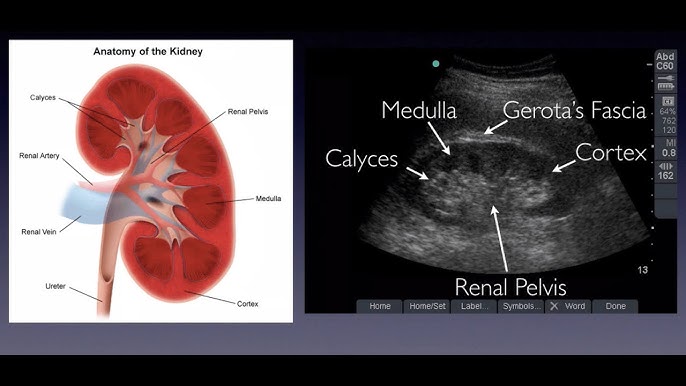

3. kép:

A vese ultrahangos képe

Ezen a képen a vese sematikus ábrája és mellette az ultrahangos képe látható.